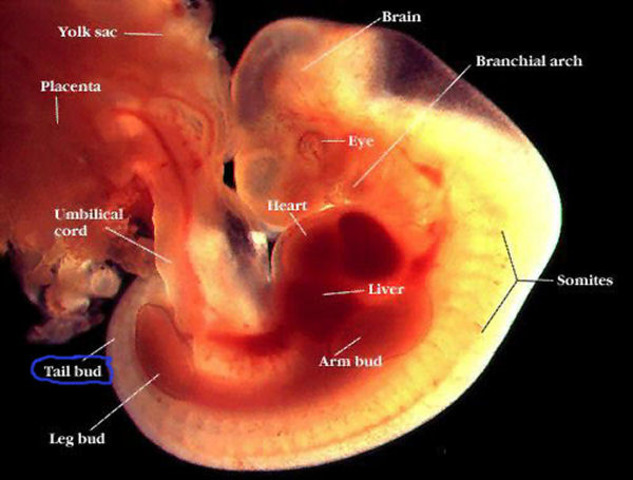

DESARROLLO FETAL: SEMANA 4

En esta semana, se puede observar el tubo neural, bordeado por somitas, de donde surgirán la columna vertebral y las costillas. El corazón empieza a latir aunque sus cavidades no están totalmente desarrolladas.

DESARROLLO FETAL: SEMANA 5

Se conforma la estructura básica del cuerpo. Principia el desarrollo de los ojos, de los oídos, de la boca y de la nariz. Se observan los brotes que van a dar origen a los brazos y a las piernas. La prominencia cardíaca es muy visible. Se desarrollan las vesículas cerebrales.